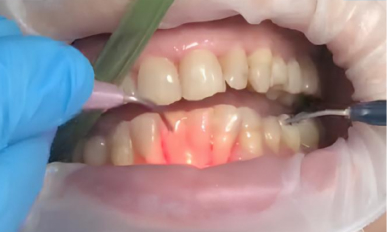

2. Лазерная обработка: Диодный лазер Medency Primo Triplo был настроен на длину волны 635 нм в режиме «периодонтит», с пародонтологической насадкой 400 мкм. Лазерный луч осторожно направляли на воспаленные ткани пародонтальных карманов для удаления бактериального налёта, стимуляции заживления и уменьшения глубины карманов.